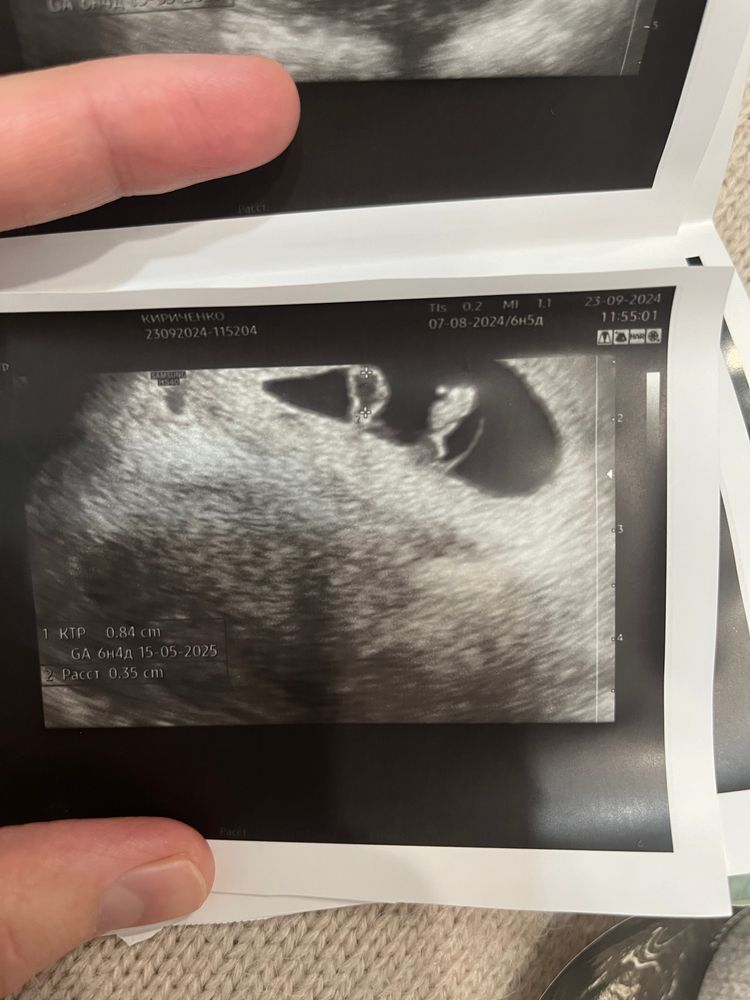

Алена, Нашла😄 Не знаю какой из них подойдет 😅все скинула Изображение Изображение Изображение

Виолетта, у вас не понятно) по середине 🤣

Виолетта, ну вот с сыном понятно) а сейчас на первой фотке если не приближать будто кот сидит 🤣